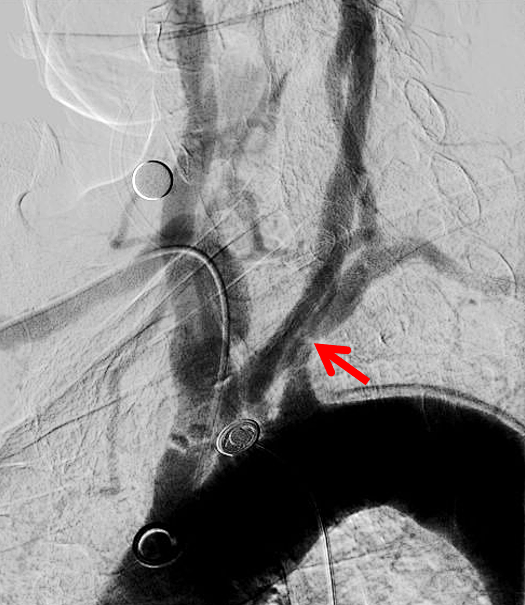

III型弓;左侧锁骨下动脉重度狭窄

经左桡动脉逆向造影显示左侧锁骨下动脉重度狭窄

6F NeuronMax 建立良好的支撑【白箭头】,支架顺利对位

NeuronMax头端顺应性良好【白箭头】,球囊扩张支架充分